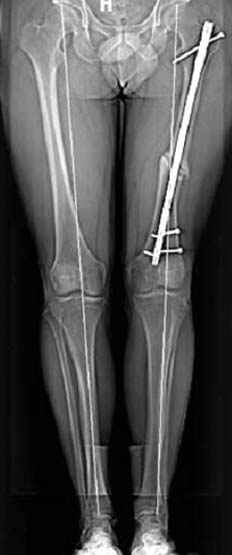

Выставлена на обсуждение (только одна проекция) рентгенограмма больного 25 лет, поступившего в приемное отделение, молодой дежурный врач сомневается в тактике лечения и спрашивает совета.

С его слов, больной стабилен,травму получил в результате автоаварии.Подскажите, что делать?Джолдас Кульджанов

5:24 Рентгенограмма таза, вызывают врача ортопеда (снимок N1), его диагноз: закрытый переломо-вывих правого тазабедренного сустава, получает добро на закрытую репозицию в приемном отделении

5:38 Дважды неудачная попытка закрытой репозиции в приемном отделении

N 2

6:20 ответстенный врач принимает решение о репозиции в условиях операционной, предупреждаются родственники и больной, что при неудачной закрытой репозиции, о возможности открытой репозиции и фиксации задней стенки вертлужной впадины.